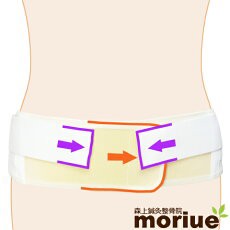

骨盤ベルトで固定したら、すぐ良くなりました。

骨盤ベルト

骨盤ベルト  腰痛ベルト